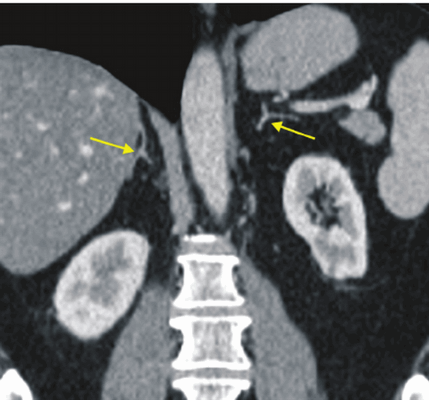

(Справа) На КТ с контрастированием у пациента с раком пищевода и метастазами в надпочечниках обнаружены гетерогенные дольчатые образования надпочечников с обеих сторон. Перед плановой эзофагэктомией была выполнена ПЭТ/КТ. Это образование оказалось ФДГ-положительным, что привело к отмене запланированной эзофагэктомии. (Слева) МРТ, Т2-ВИ, аксиальная проекция: у пациента с феохромоцитомой выявлена крупная гетерогенная опухоль левого надпочечника, гиперинтенсивная на Т2-ВИ и гипоинтенсивная на Т2-ВИ. Такая картина характерна, но не патогномонична для феохромоцитомы. Диагноз был подтвержден посредством резекции.

(Справа) МРТ, Т2-ВИ, коронарная проекция: у этого же пациента выявлена гетерогенная гиперинтенсивная опухоль, что характерно для феохромоцитомы. (Слева) На рисунке показаны локализации феохромоцитомы (синим) и параганглиомы (зеленым). Обратите внимание на орган Цуккеркандля в области бифуркации аорты.